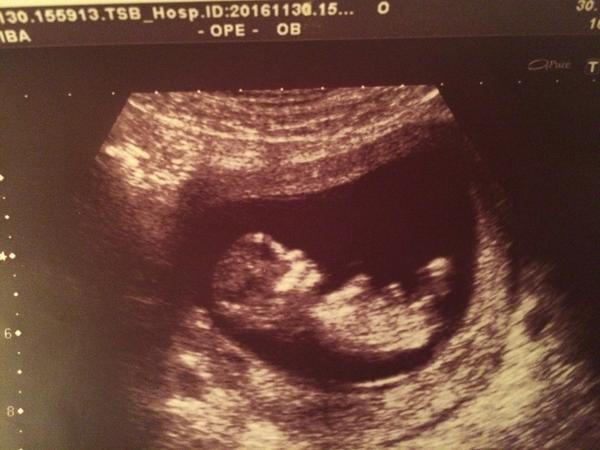

Je to holčička nebo chlapeček? Foto ultrazvuku

tak musim rict, ze u nas se na 1. screeningu lekari trefili i napodruhé.. poprvé to byl kluk, ted podruhe holka..... fotky uz jsem davala...